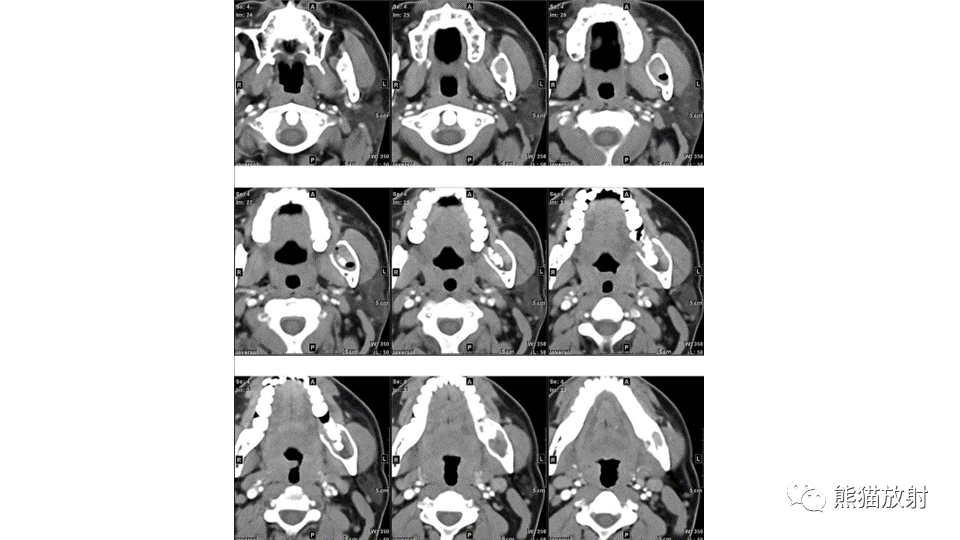

【病例】下颌骨成釉细胞瘤2例CT-4

【病例】下颌骨成釉细胞瘤2例CT-5

【病例】下颌骨成釉细胞瘤2例CT-6